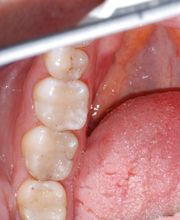

Das Bodensee Implantat Zentrum (ZIP) ist Ihre führende Praxis für Zahnheilkunde in der Region. Wir sind spezialisiert auf hochwertige Implantologie, einschliesslich des All-on-4® Konzepts, für das wir als Excellence Center Gold-zertifiziert sind. Unser Leistungsspektrum umfasst Komplettsanierungen, Kronen, Brücken sowie ästhetische Behandlungen. Mit über 30 Jahren Erfahrung bieten wir auch Angstpatienten eine einfühlsame Betreuung und Behandlungen unter Narkose für ein strahlendes Lächeln.